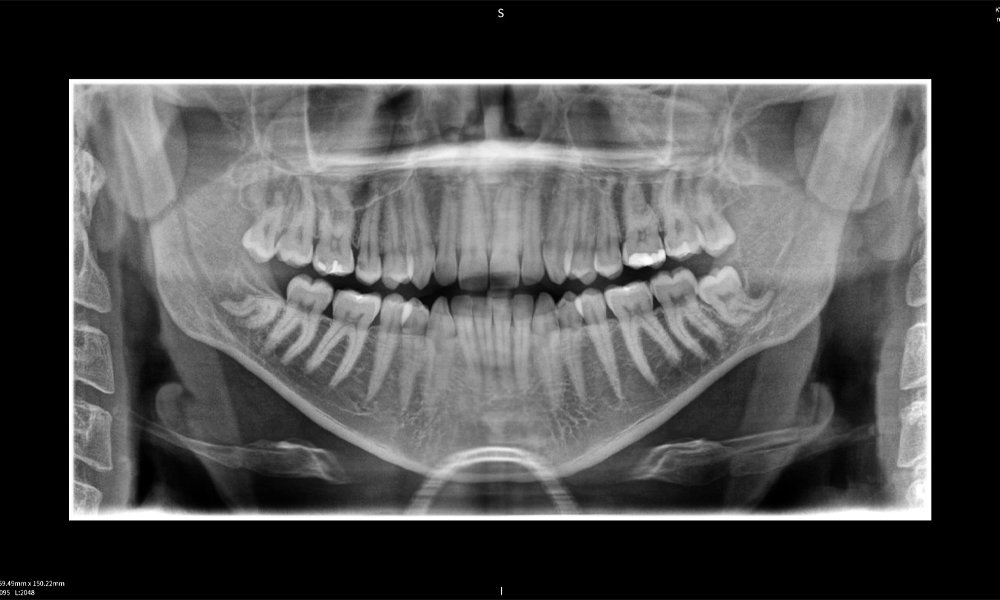

Figura e: Resultados de imagen de Seethrough Max, sobre un fondo negro.

Figura e

Figura e: La radiografía panorámica sirve como herramienta de evaluación inicial, mostrando la posición general de los dientes, así como posibles cambios patológicos. Es notable que en el lado derecho (diente 48) se observa la situación posterior a una amputación de corona realizada por un profesional externo. Las dos raíces fuertemente curvadas permanecen en estrecha proximidad topográfica al nervio alveolar inferior dentro del hueso. Esto sugiere una decisión deliberada de evitar el mayor riesgo de lesión nerviosa durante una extracción completa y representa un hallazgo clínicamente relevante. En resumen, las tomografías CBCT con Seethrough Max proporcionan información crucial sobre la anatomía compleja y la relación crítica entre las muelas del juicio y el nervio alveolar inferior. Esta imagenología diagnóstica detallada preoperatoria es esencial para realizar procedimientos quirúrgicos seguros y exitosos en la región mandibular.